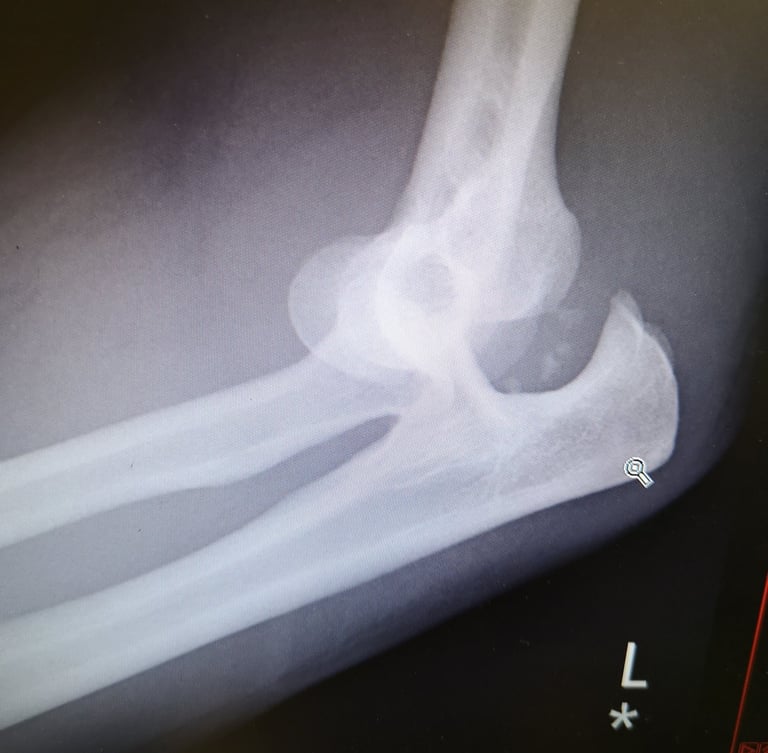

A serious fracture injury can require surgery, immobilisation, and extensive rehabilitation, making it essential to seek legal advice from a personal injury solicitor near you.

Recovery from a fracture often involves physiotherapy, pain management, or even surgical intervention such as fixation with plates or screws. Without proper treatment, fractures can lead to chronic pain, reduced mobility, arthritis, or complications such as delayed healing or infections. Compensation can help cover medical treatment, rehabilitation, lost earnings, and ongoing care to support your recovery.

Examination by expert orthopaedic surgeons to get every detail of your injury evidenced and compensated.